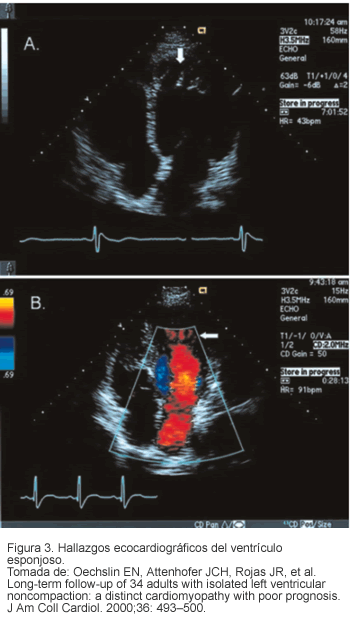

Ecocardiograma bi-dimensional Doppler a color

Es el estándar de oro diagnóstico porque demuestra la presencia de múltiples trabéculas ventriculares prominentes, así como el flujo sanguíneo entre las trabéculas o sinusoides en continuidad con la cavidad ventricular (23). En el ventrículo izquierdo los segmentos con mayor compromiso son la región apical, la pared inferior y la pared medio-lateral (80%) (Figura 3). En el ventrículo derecho la afección se da en la región apical (41%) (28). Se observa disfunción sistólica con una fracción de eyección estimada de 33% en las diferentes series (7) y disfunción diastólica con patrón restrictivo de llenado en 36% de los casos. Además, se ha observado hipocinesia tanto en miocardio afectado como sano (teoría del daño microcirculatorio coronario global) (24, 25).

Otros métodos diagnósticos útiles son: ventriculograma con contraste, tomografía computarizada cardiaca, tomografía con emisión de positrones y resonancia magnética principalmente para definir la localización y extensión del miocardio lesionado (17, 18).